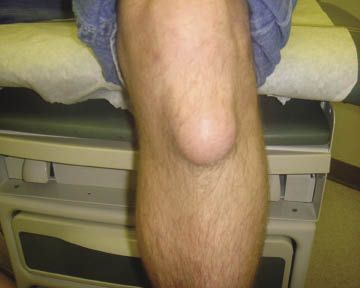

Question 1:

For 2 months, a 29-year-old man had pain and circular, soft swelling over the anterior left knee, superficial to the patellar ligament. Pain was minimal and associated with extension and flexion. He had been employed laying floor tile for 10 years.